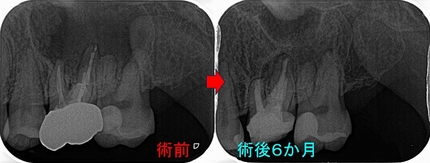

レントゲン

レントゲンに収まらないぐらい大きな根尖病変があります。(開業以来トップ5に入るぐらい大きな病変)

また腫れを感じるとのことで来院して頂いた時のレントゲン

レントゲンでは術前に比べ骨は出来てきている所見アリ

原因の根はMB根だと分かってきたので、ここで外科的歯内療法を行いました。